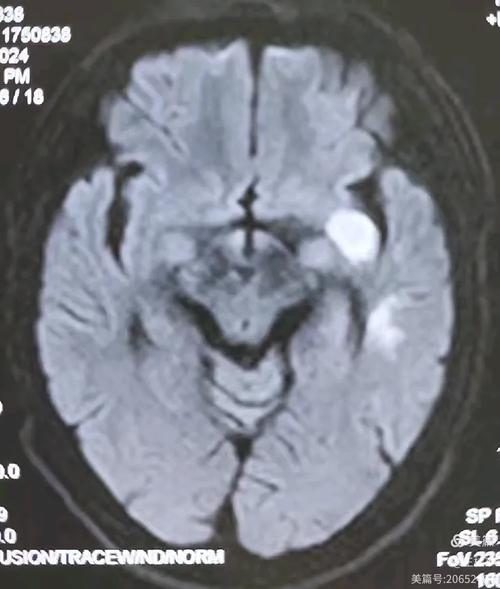

(图片来源网络,侵删)MRI可以精确地显示梗塞灶的大小、形状和具体位置,帮助医生判断是哪个血管堵塞,以及脑组织受损的程度,这对于制定治疗方案和评估预后至关重要。